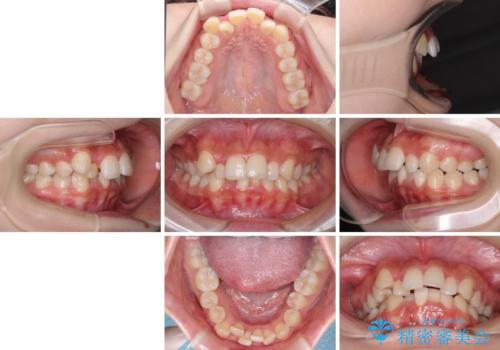

- 上顎の八重歯と、上下前歯のデコボコを気にして来院された患者様です。

奥歯の咬み合わせを見ると、上顎臼歯が下顎に対して前方にあり、叢生改善により口元が突出する顔貌ではなかったため、上顎左右第一小臼歯2本を抜歯し、ワイヤー装置にて矯正治療を行うこととしました。

前歯部のデコボコがなくなったため、歯磨きしやすくなり、非常に清潔な状態になりました。